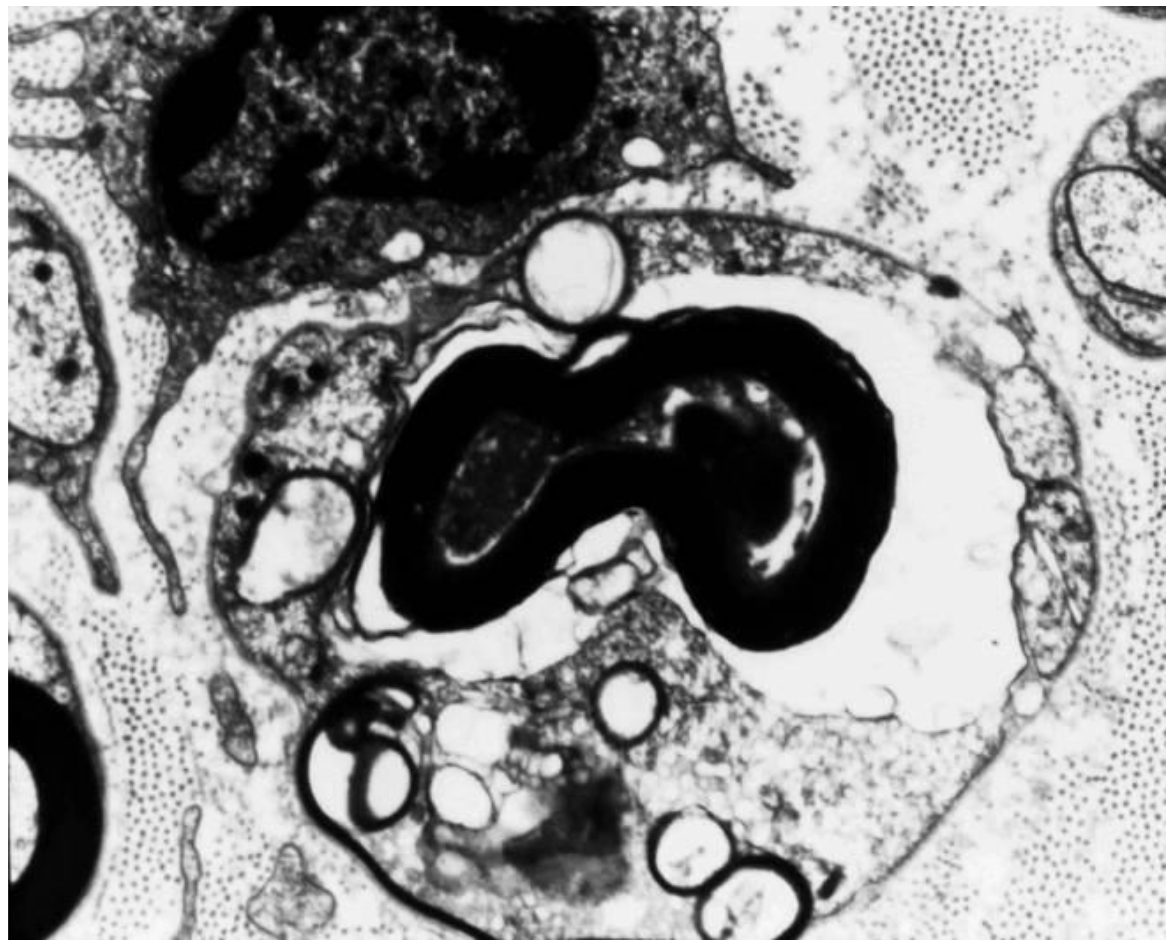

What can be seen in the image below?

Normal myelinated nerve fiber:Which axonal and Schwann cell organelles can you see?.

Note collagen fibers in the endoneurium

Neural tubules and filaments seen in the middle.

Myeline sheath appears black b/c of fixative used (osteum? preserved myelin sheath).